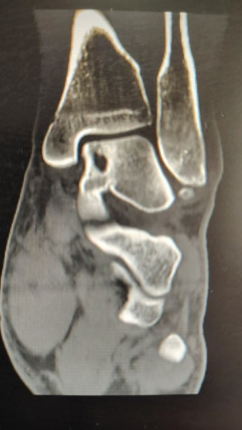

副主任医师李亚峰经过详细的评估,确定小刘是距骨骨软骨损伤

距骨是足部重要的负重骨,向上和胫骨腓骨相关节,下方和跟骨相关节,前方和舟骨向关节,距骨表面大部分为软骨覆盖

距骨骨软骨损伤是踝关节软骨损伤中的一种常见类型,是踝关节骨折和运动损伤的常见病,主要表现为距骨滑车部分关节软骨剥脱,并影响到深部的软骨下骨

随着距骨骨软骨损伤的发展,时间久了软骨下骨中,部分骨质被慢慢吸收,骨组织减少,里面逐渐变成一个空腔,即“囊变”

囊变

Cystic degeneration